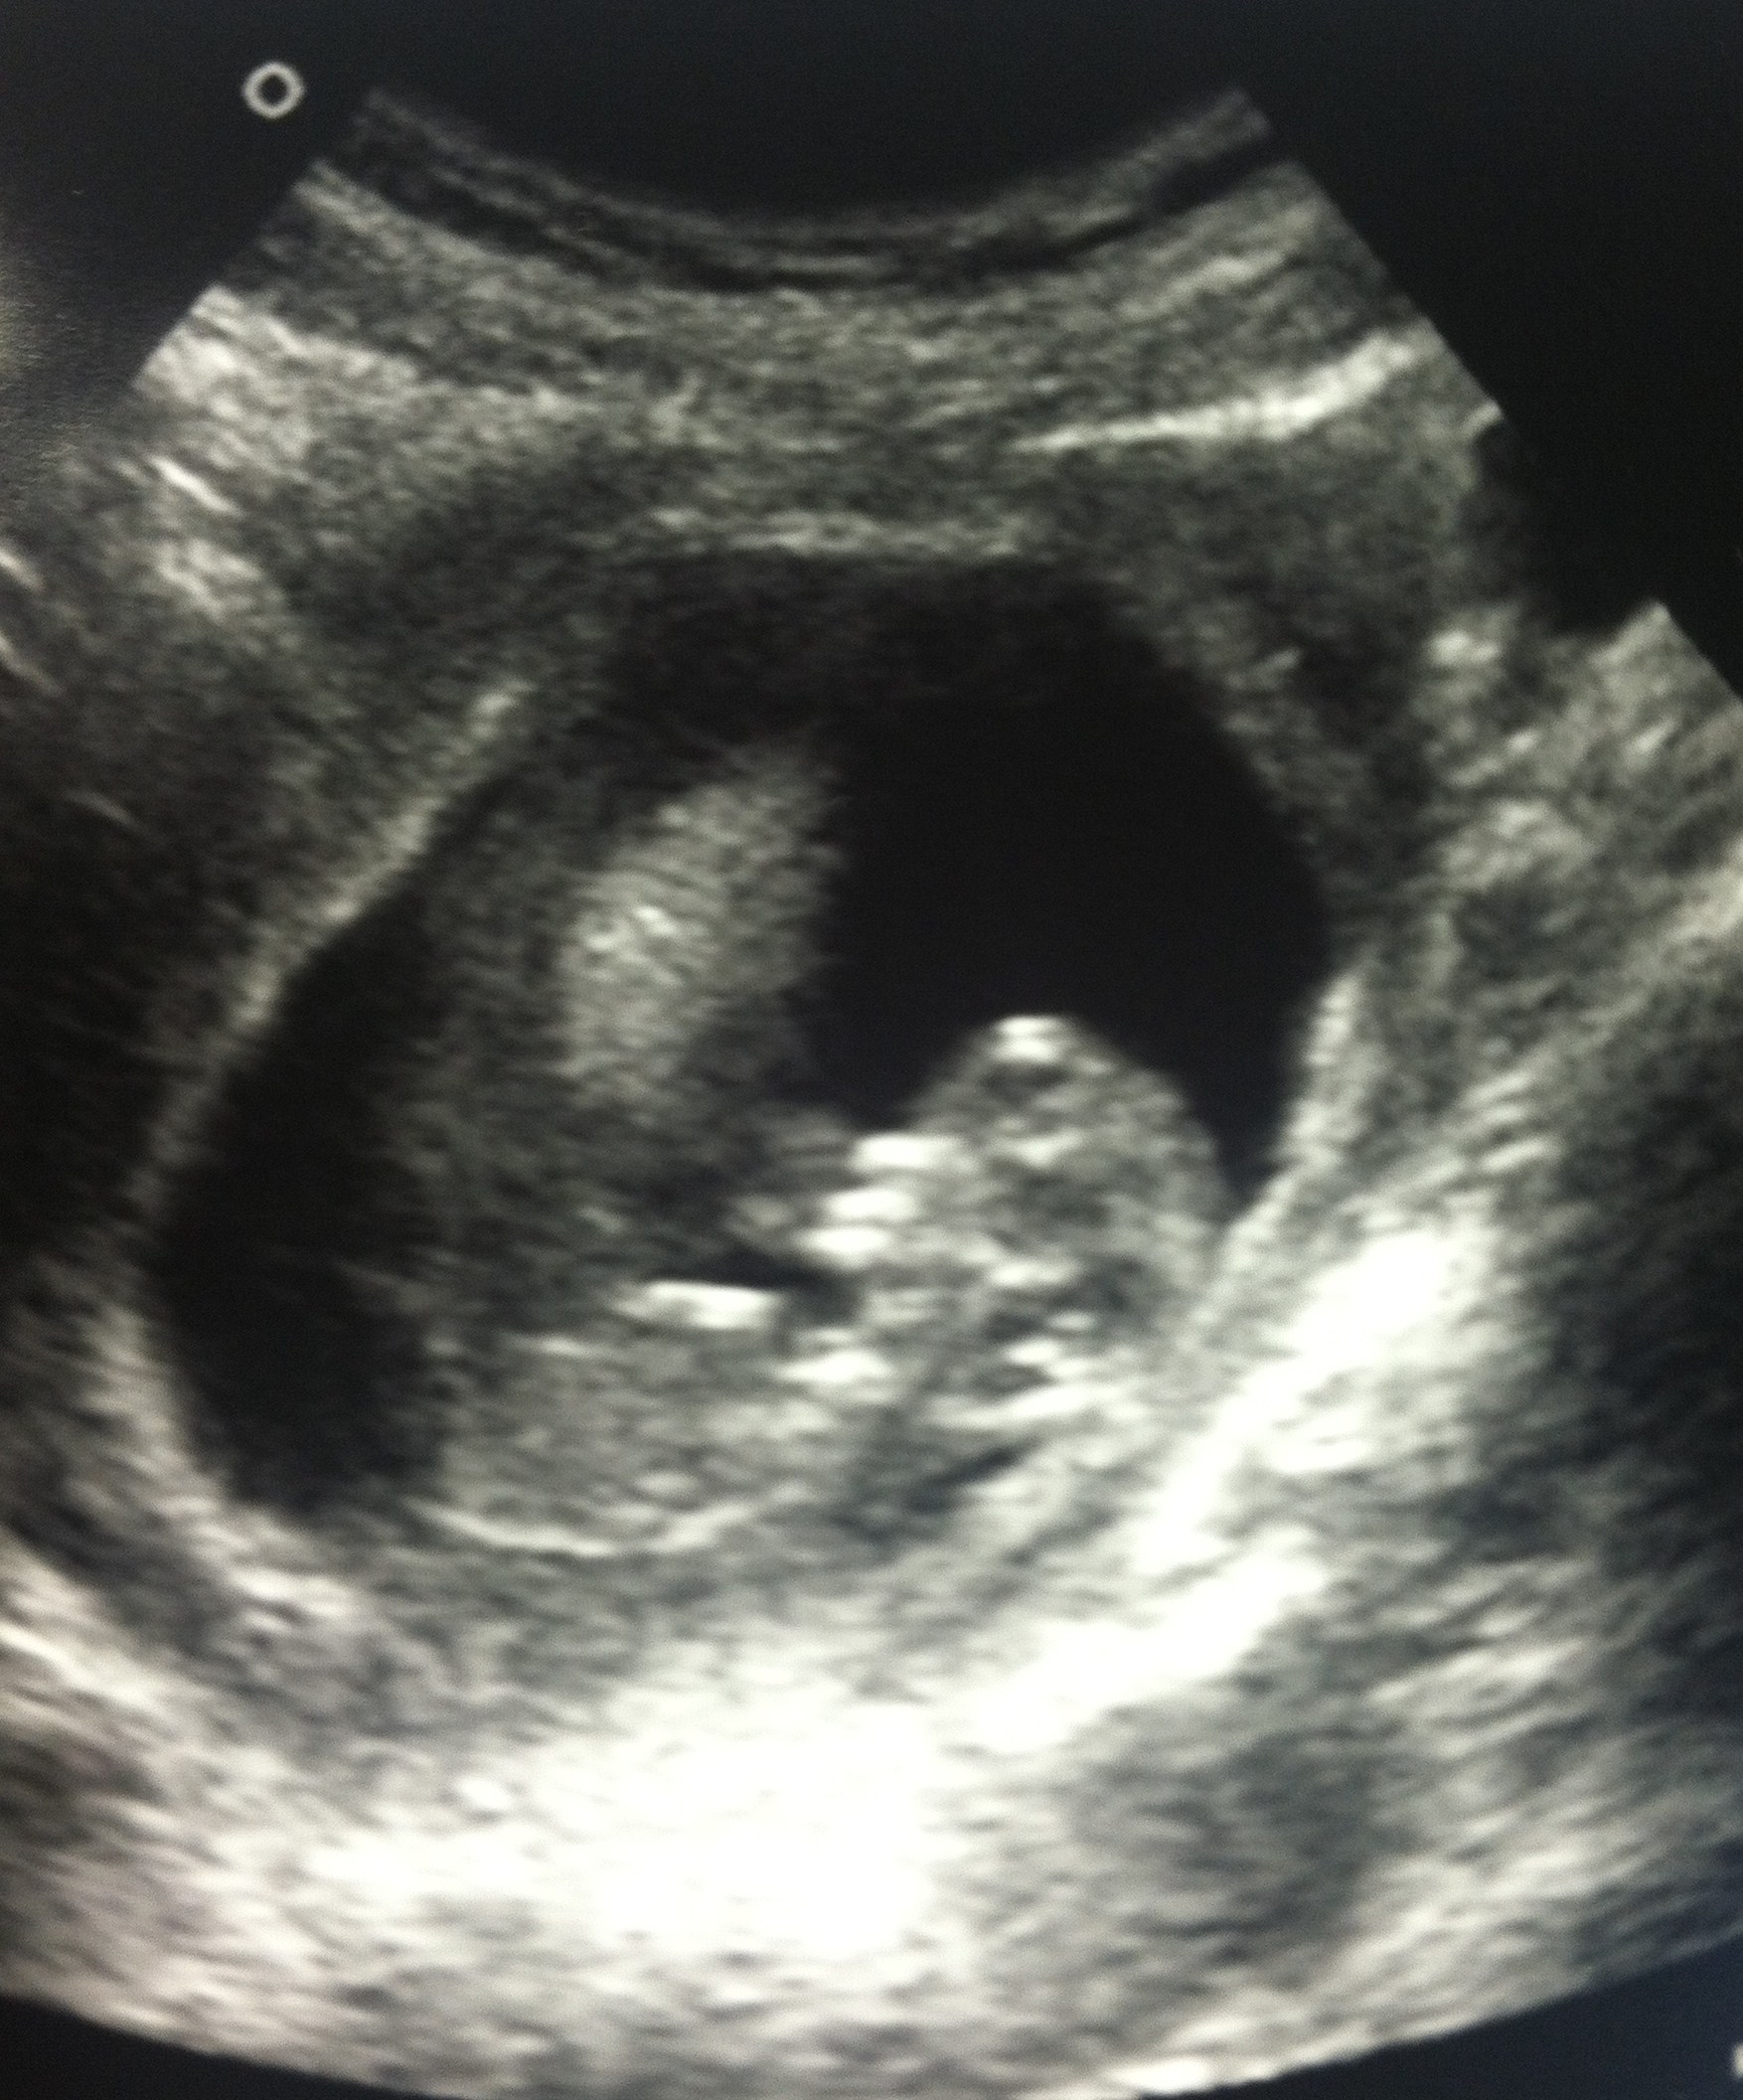

I am due March 21st, which makes me 13 weeks pregnant already. Want to know the best part??

It’s a

BOY!

Yep, thanks to modern medicine and a simple genetic blood test, we found out the gender at just 12 weeks! Pretty incredible.